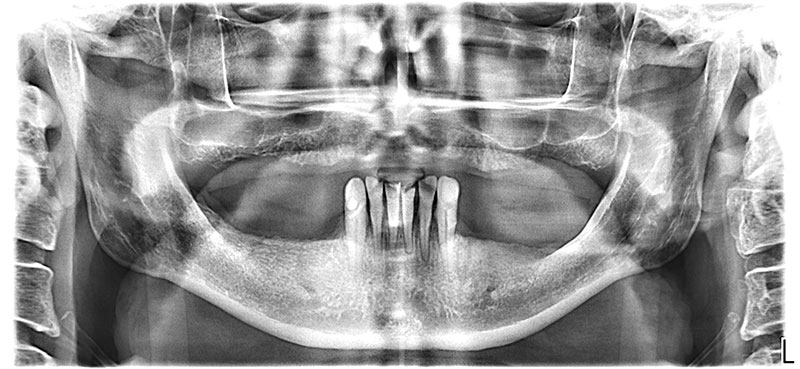

ОПТГ до операции

Полное отсутствие зубов на верхней и частичное на нижней челюсти. Неудовлетворительная эстетика оставшихся зубов. Эмоциональный дискомфорт из-за отсутствия зубов.